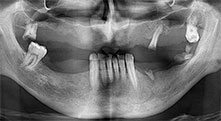

Bratu: Wir nutzen die Instrumente routinemäßig für die Entnahme von Knochenblöcken und das Spalten von Kieferkämmen. Weiterhin osteotomieren wir mit den Piezomed B6/B7 retinierte Zähne und entfernen nicht erhaltungsfähige Implantate. Alles Indikationen, bei denen es auf tiefe, saubere Schnitte ankommt.

Bratu: Wir bevorzugen Knochenentnahmen von der Linea obliqua externa des posterioren Unterkiefers, nicht aus der interforaminalen Region. Nach der Weichgewebsinzision verwenden wir die neuen Sägen, um den Umfang der Knochenentnahme zu definieren. Wir erledigen damit in fast 80 Prozent der Fälle auch die gesamte Präparation. Zusätzlich verwenden wir eventuell andere Piezo-Instrumente und zuletzt einen Meißel, um den Block zu mobilisieren. Das ist für uns eine sehr effektive Operationstechnik.